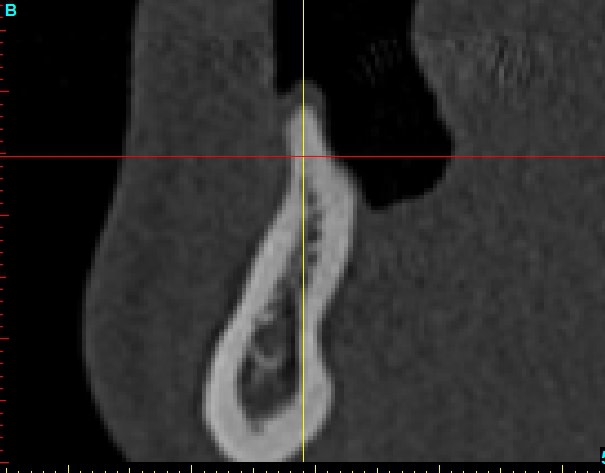

Coupe xray transversale omynvk - Eugenol

Coupe xray transversale greffe m05aen - Eugenol

Coupe xray transversale greffe2 njaaal - Eugenol